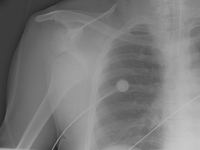

Scapular Y x-ray view showing an anterior fracture dislocation of the shoulder and fracture of the greater tuberosity

Personal collection of Dr Paul Novakovich